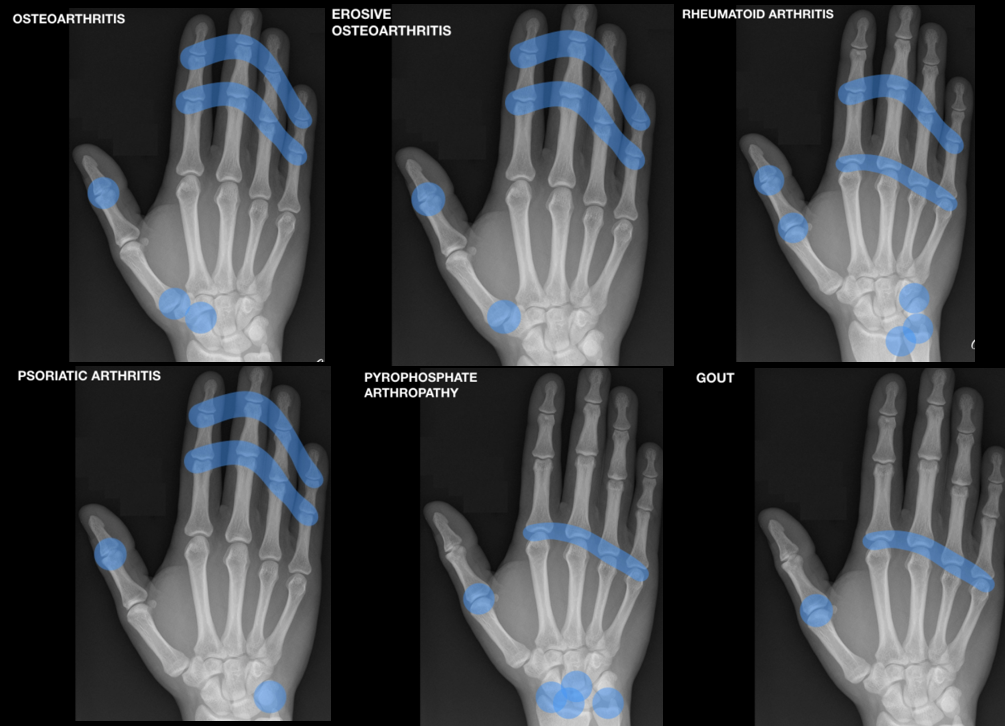

Schema des mains

osteoarthrite arthrite arthrose erosion erosive kellgren seagull gull wing érosive